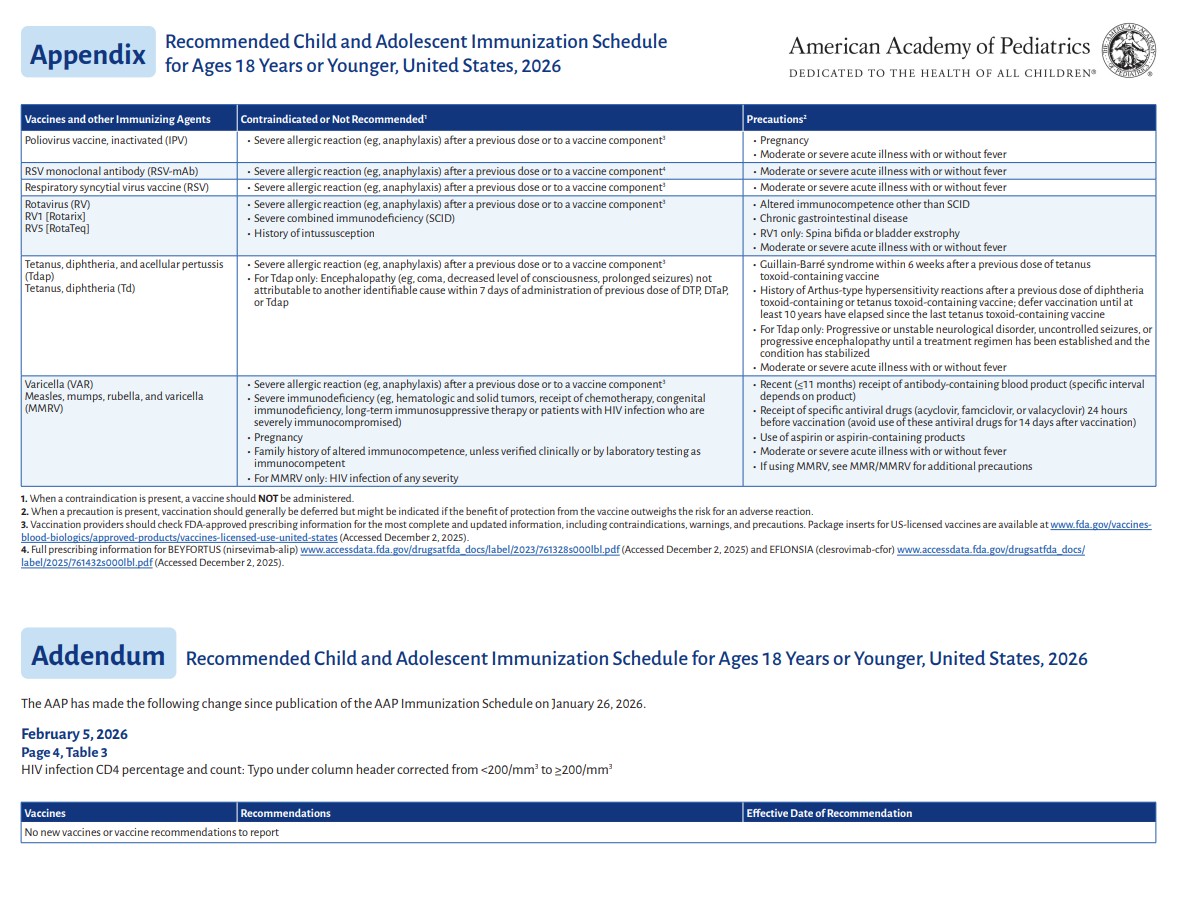

p 1